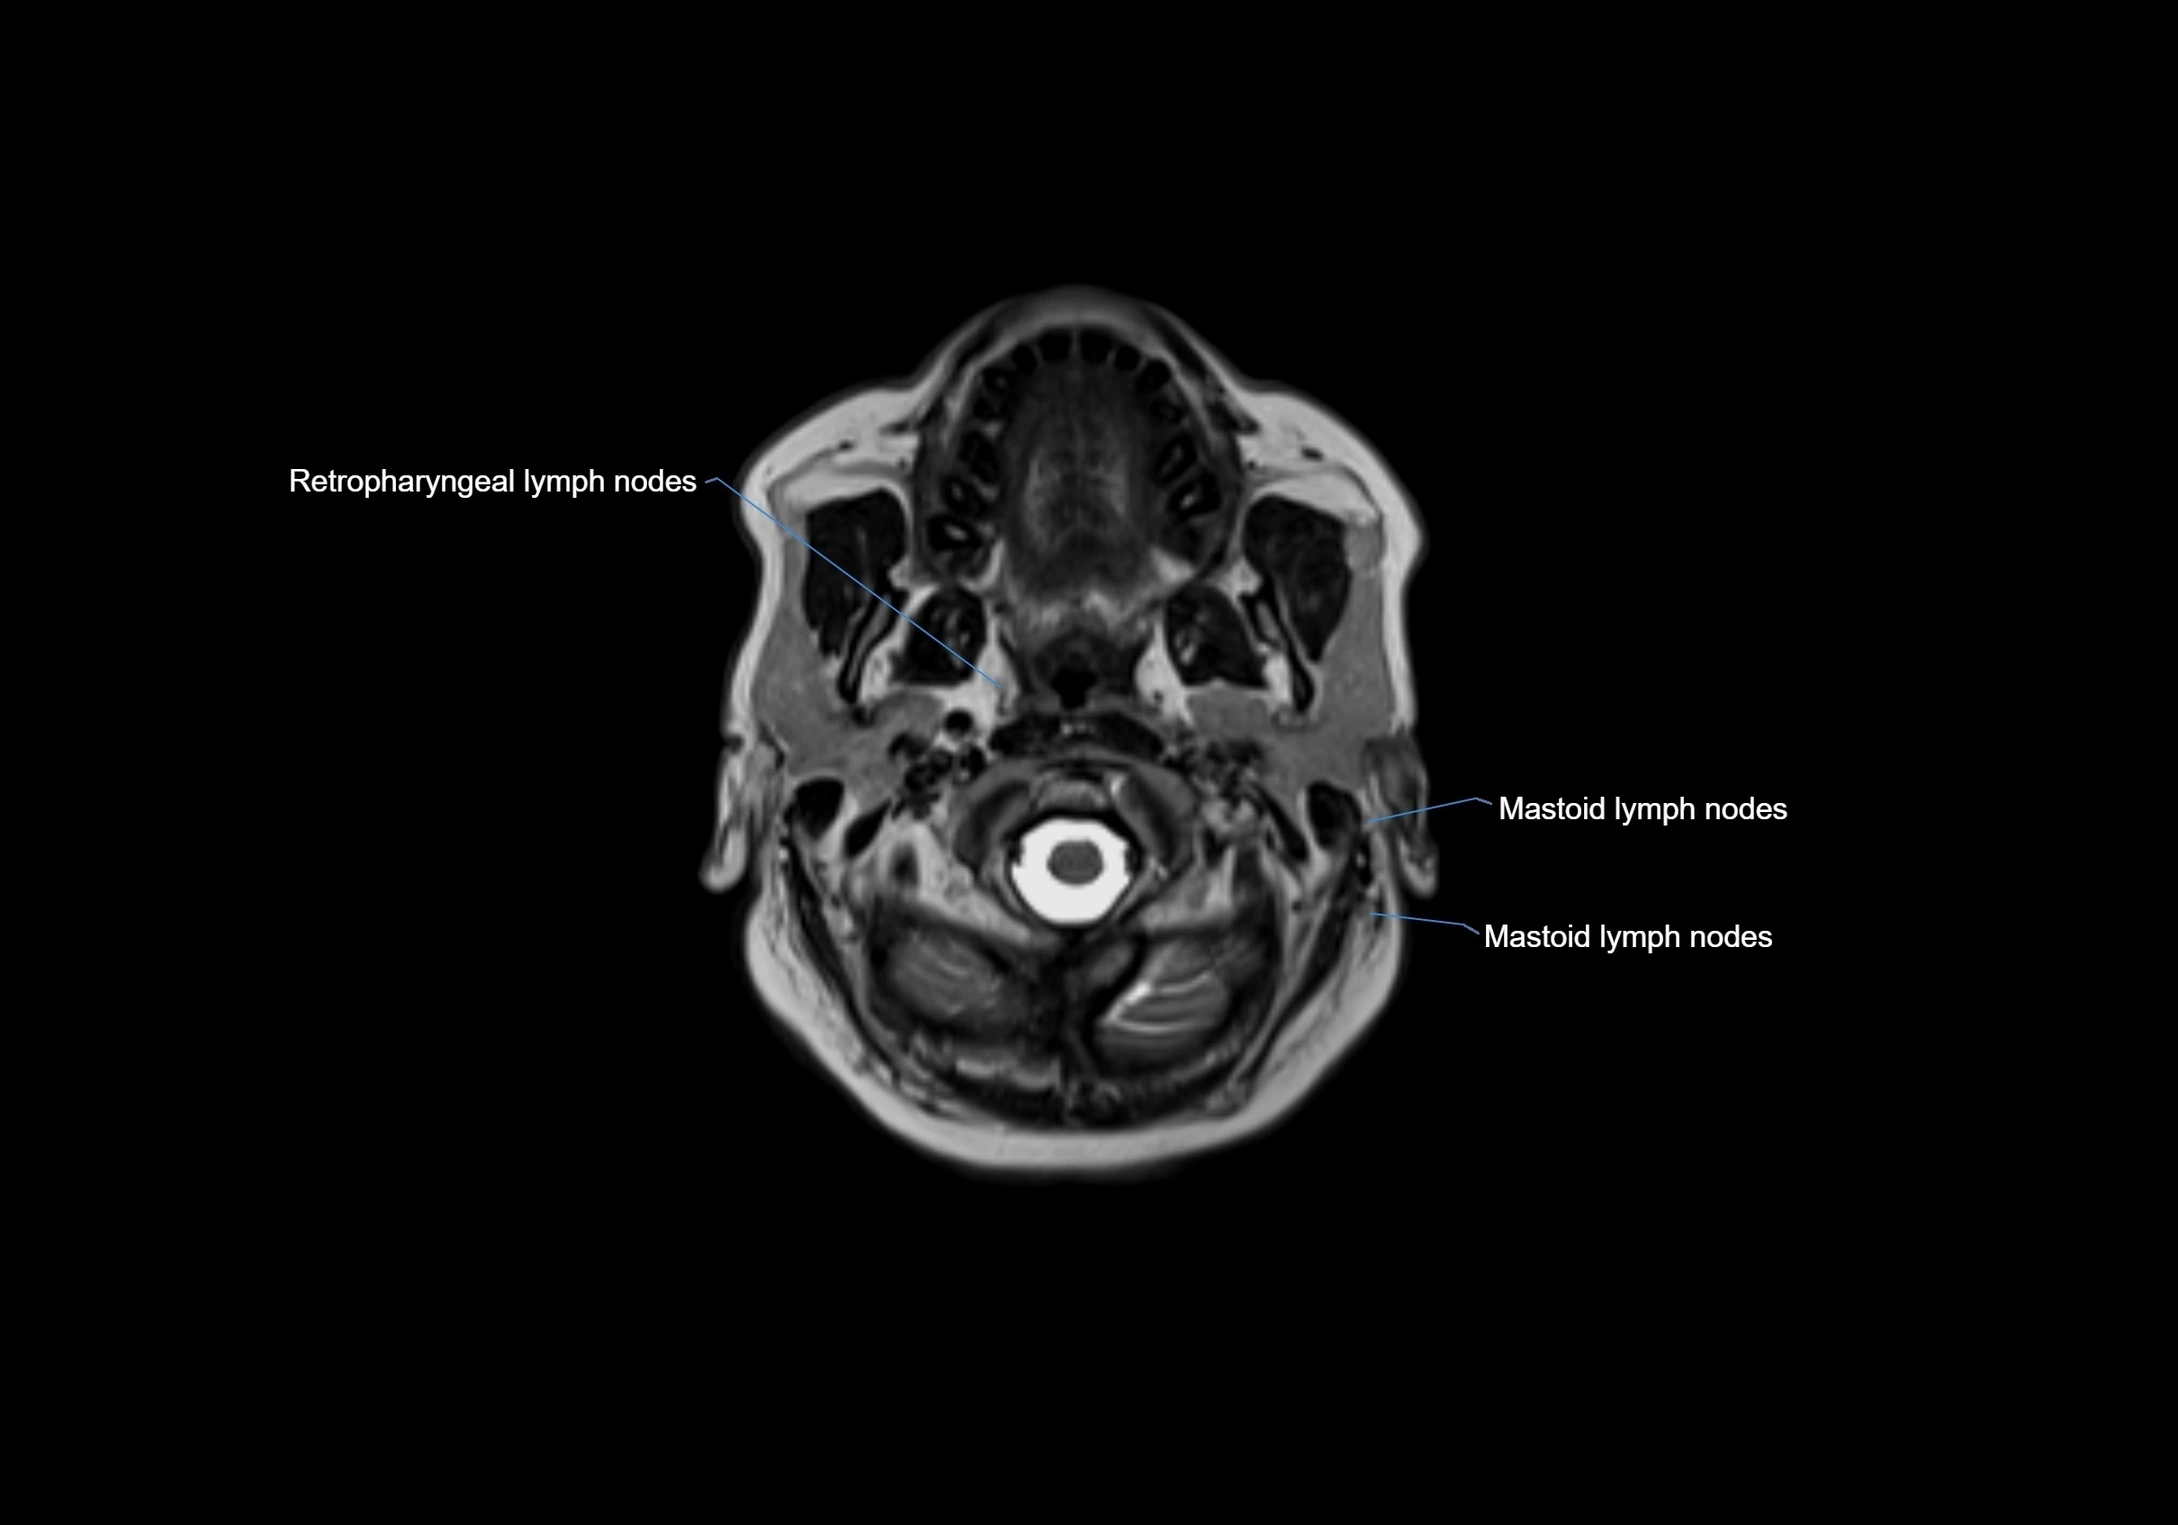

MRI Appearance

T1-weighted images:

• Normal accessory nodes appear as small, oval hypointense to intermediate signal structures within subcutaneous fat

• Surrounded by hyperintense fat, enhancing contrast for visualization

• Pathological nodes may appear enlarged or rounded, sometimes with cortical thickening

T2-weighted images:

• Nodes show intermediate signal, with surrounding fat bright

• Useful for detecting edema, inflammation, or infiltration

• Fatty hilum may appear slightly hyperintense relative to cortex

MRI images

image